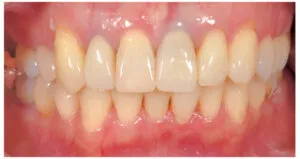

治療内容:前⻭6本のダイレクトベニア

治療費用:¥440,000(税込み)

リスク:噛み合わせにより欠けることがあります

治療回数:2回